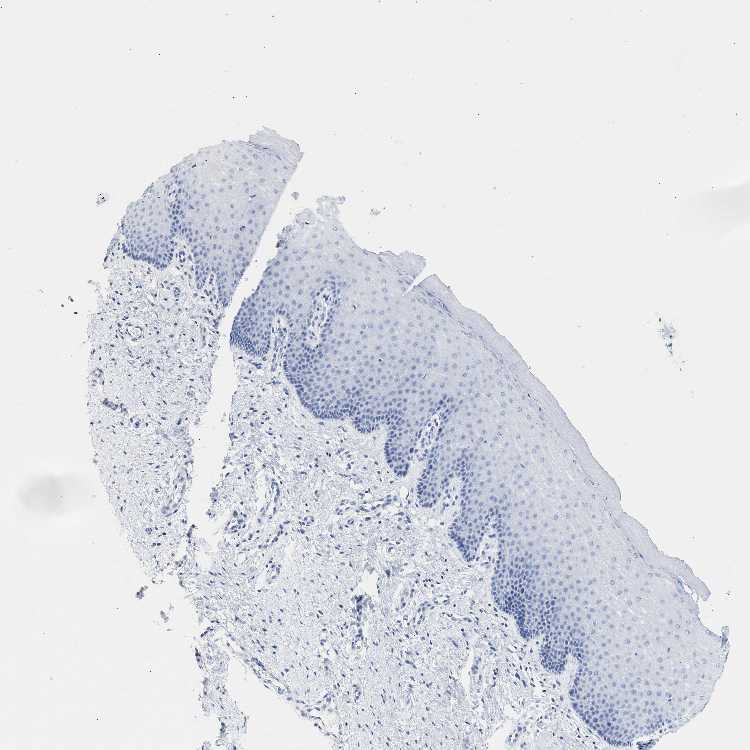

CERVIX - Antibody stainingi

Antibody staining in the annotated cell types in the current human tissue is reported as not detected, low, medium, or high, based on conventional immunohistochemistry profiling in selected tissues. This score is based on the combination of the staining intensity and fraction of stained cells.

Each image is clickable and will lead to virtual microscopy that enables deeper exploration of all samples and also displays staining intensity scores, fraction scores and subcellular localization as well as patient and tissue information for each sample.

Antibody HPA017753

Glandular cells Not detected

Squamous epithelial cells Not detected